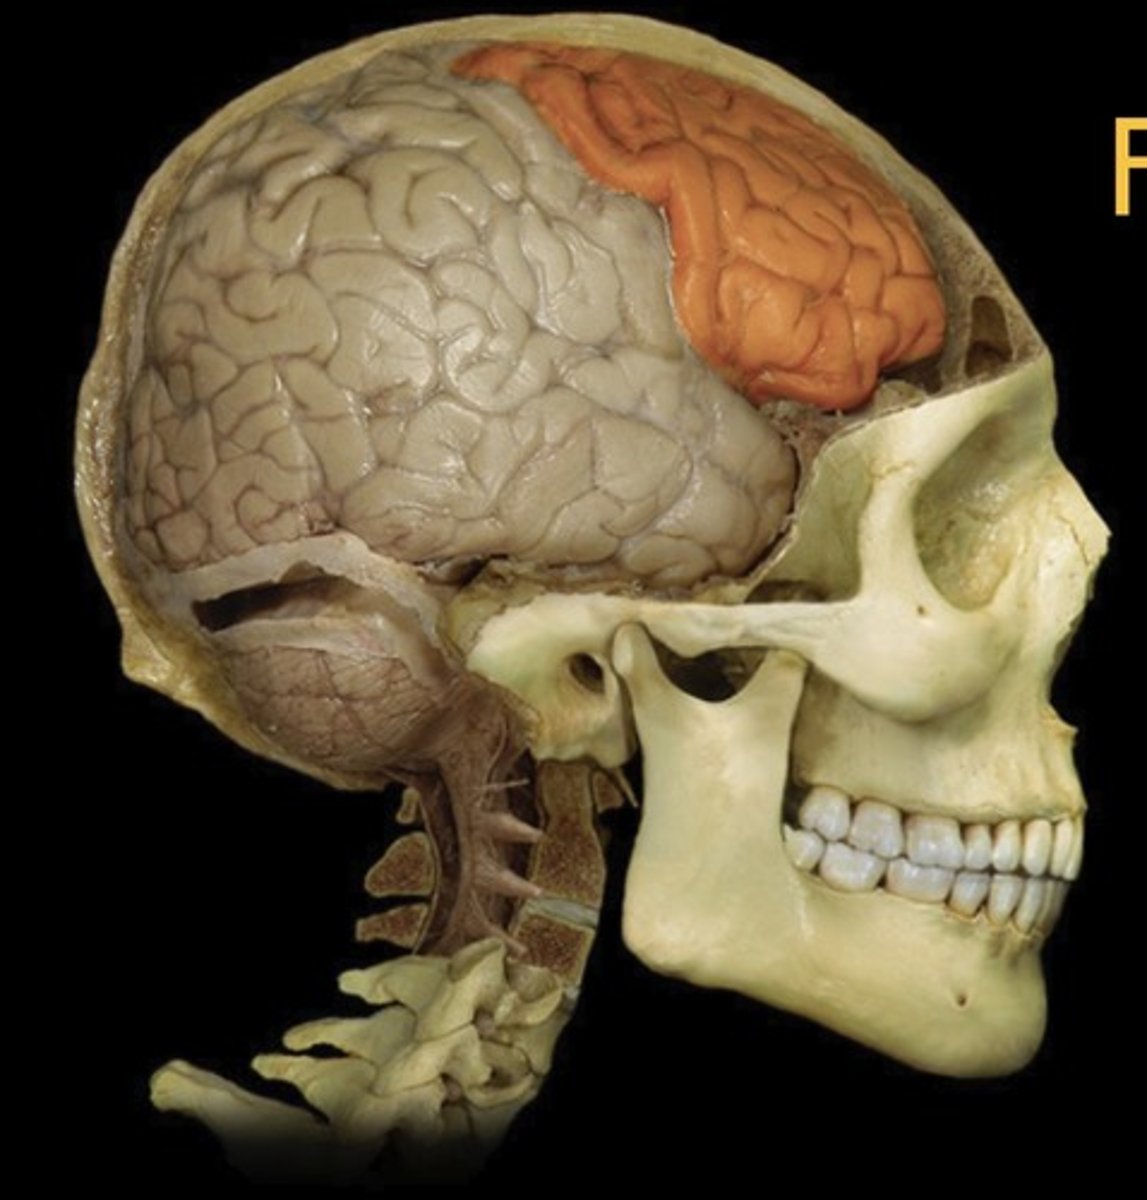

Frontal Lobe

Name this structure

Parietal Lobe

Name this structure

Temporal Lobe

Name this structure

Occipital Lobe

Name this structure

Cerebellum

Name this structure

Lateral Sulcus

Name this structure